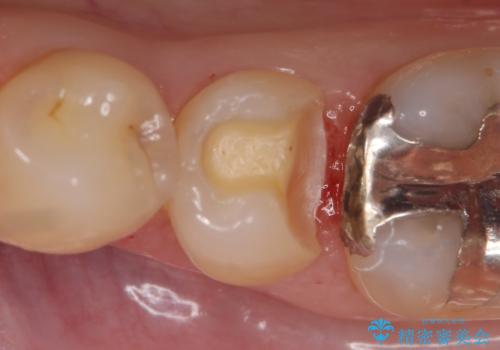

- 他院にて左下5の虫歯治療を行おうとしたところ、歯の神経治療をすると言われたため、できれば神経を残せないかと当院にいらっしゃった方の症例です。

自発痛・持続痛等の症状がなく、露髄(歯の神経が露出してしまうこと)することなく虫歯の除去を完了したため、しばらく経過観察を行った後に神経治療をすることなく、セラミックインレーによる修復を行うことができました。